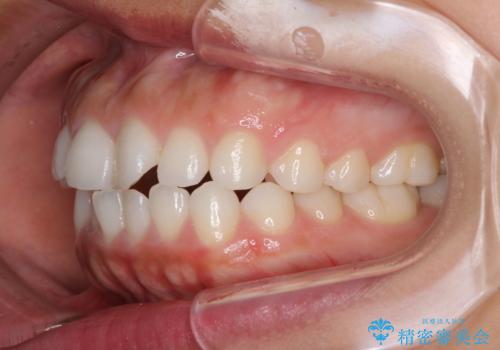

- 口元の突出感を気にして来院された患者様です。

上下左右の第一小臼歯4本を抜歯して口元を下げる治療計画としました。